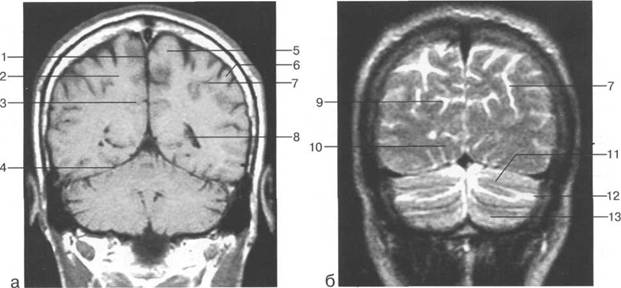

Задняя череп 13513u2010n 85;ая ямка представляет собой часть основания череп 13513u2010n 72;, ограниченную централь

Следует отметить, что в настоящее время оптимальным методом исследования структур задней череп 13513u2010n 85;ой ямки является МРТ, которая, в отличие от КТ, лишена артефактов от кост

Мозжечок заполняет практически весь объем задней череп 13513u2010n 85;ой ямки. Его поперечный раз

Следует остановиться на анатомии подпаутинных пространств задней череп 13513u2010n 85;ой ямки IV 20 мм. Между основанием череп 13513u2010n 72; и нижней поверхностью мозга от большого затылочного отверстия вдоль ската и спинки турецкого седла простирается задняя базальная цистерна. В зави IV

теменно-затылочная борозда; 11 - семиовальные